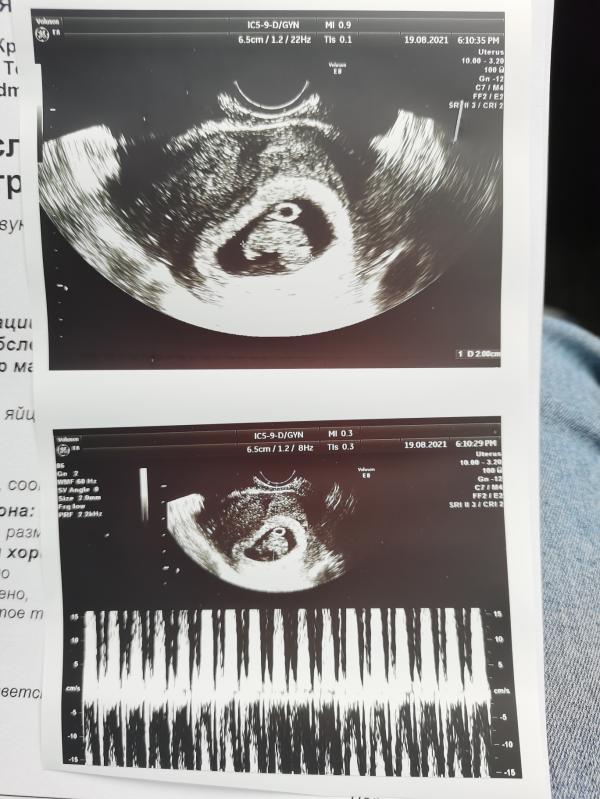

Сегодня была ещё раз на узи) растём) 2см уже) по ПДПМ 9н 3д, по узи 9 недель)